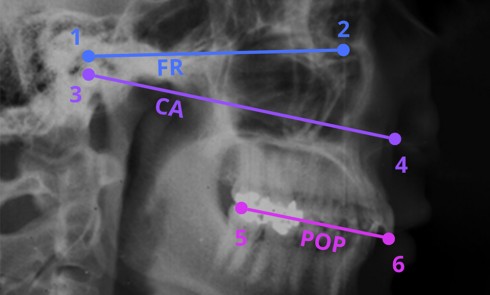

La mise en œuvre d’un traitement prothétique implique la collecte de données biologiques (fonctionnelles et esthétiques), afin de créer une...Vidéos